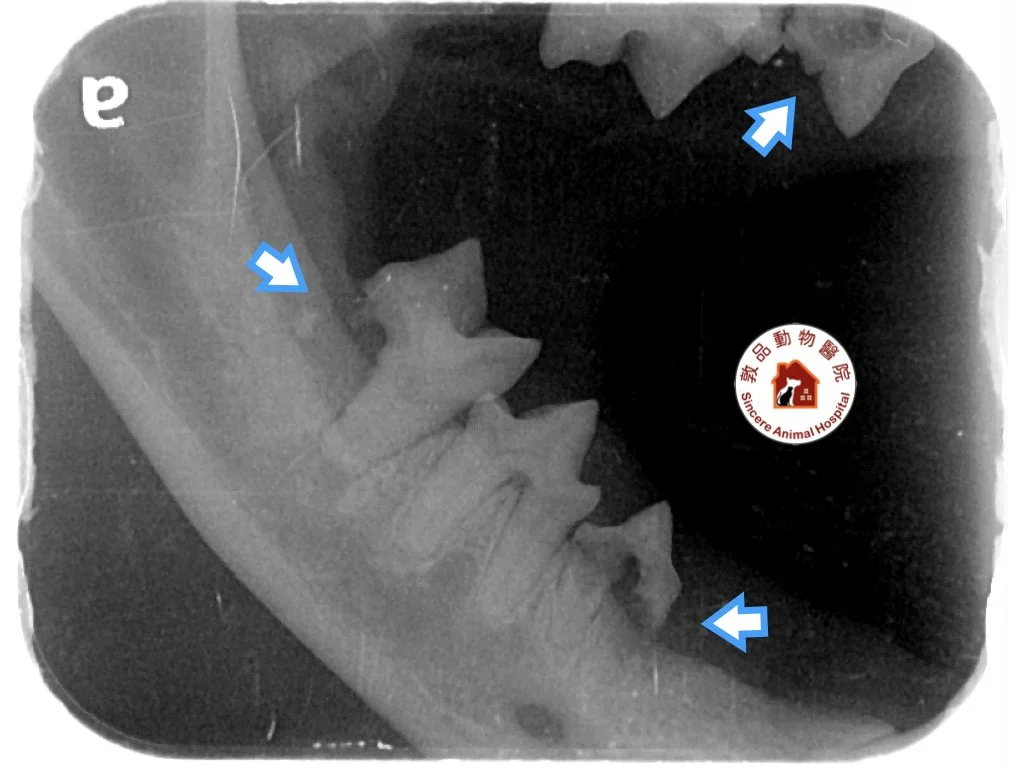

圖片中可以明顯見到上牙齒在X光下的破裂情況

牙科X光檢查(黃金準則)

全口牙科X光攝影是診斷貓齒吸收疾病的最準確方法,可以:

- 完整評估牙根狀況

- 確定疾病分級

- 制定精確的治療計劃

- 發現肉眼無法看到的早期病變